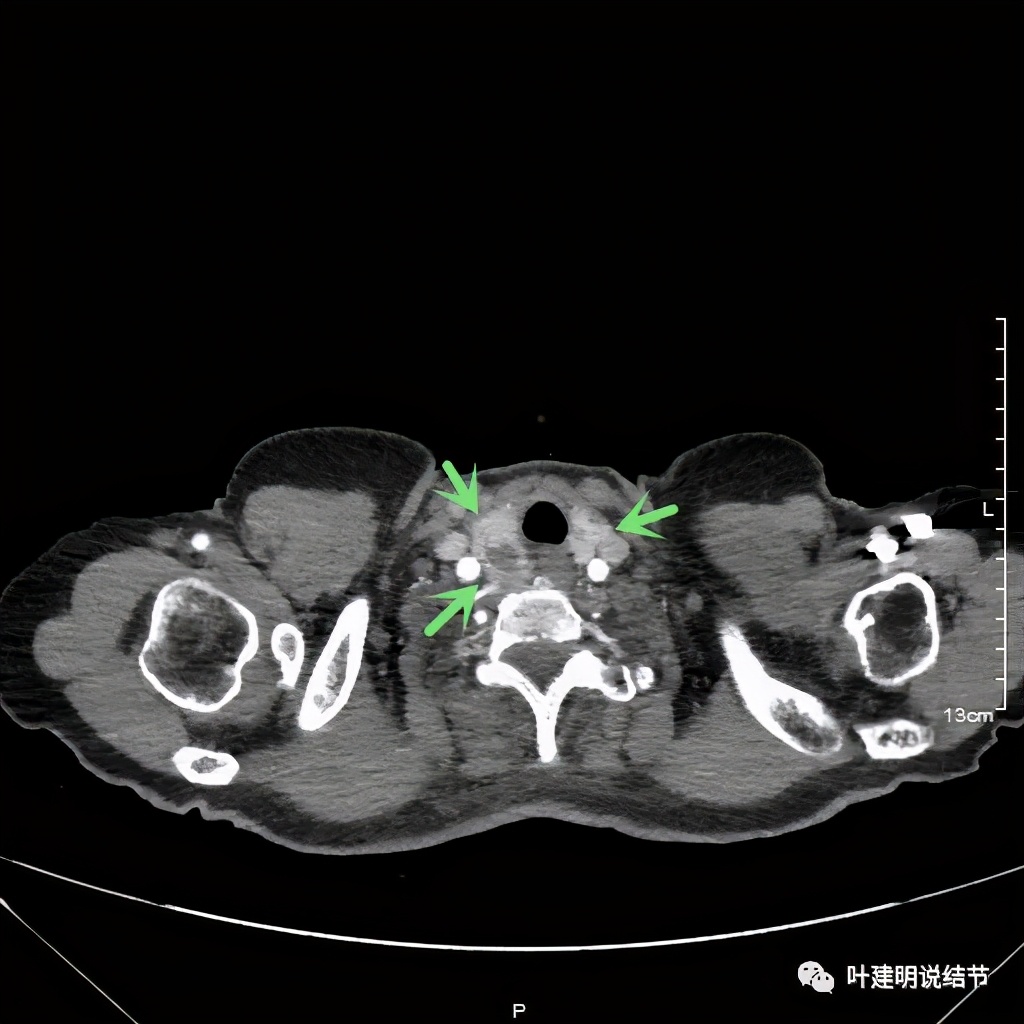

上图红色示肿瘤,黄色示气管,桔色示左无名静脉,蓝色示上腔静脉,而且肿瘤密度不均杂乱

上图红色示肿瘤,黄色示气管,粉色示肿瘤与气管关系密切,桔色示左无名静脉,肿瘤密度不均

上图红色示肿瘤,黄色示气管,蓝色示上腔静脉